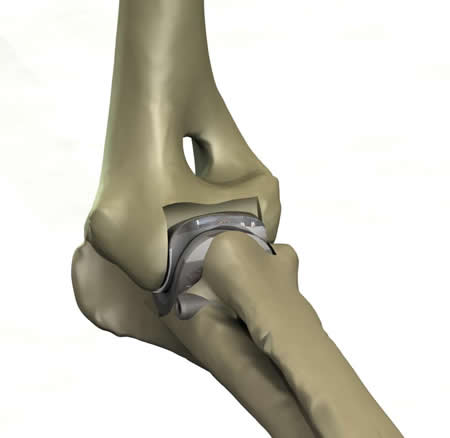

What is the TATE Elbow™?

It is a minimally invasive resurfacing arthroplasty of the canine elbow.

What is novel about the concept?

Simultaneous preparation of both joint surfaces using the axis of rotation as the mill datum has not been done before. The other unique aspect of the patent is inserting both components of an arthroplasty together as a cartridge. These concepts potentially provide for improved alignment of the implants, reduced surgical trauma and reduced surgical time.